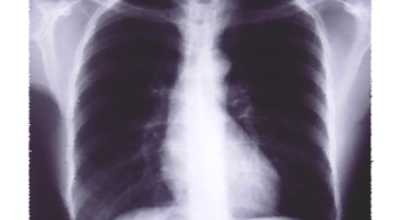

8. 갈비뼈 금간 증상 - 근육통과 금이 간 경우 차이는 거의 없습니다.

일반인이 근육통과 금이 간 경우의 차이는 거의 판별하기 힘들어요. 갈비뼈라고 하는 부분이 눈에 보이도록 붓는 것도 아니고, 멍이 들어서 아픈것도 아니기 때문이지요. 가장 정확하게 판별하는 방법은 엑스레이를 찍는 방법이지요.